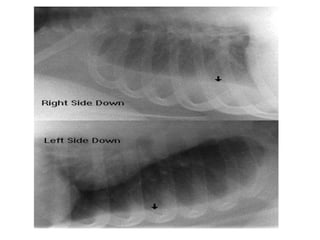

RADIOGRAPHIC EXAMINATION

Based on the decubitus films

• small effusions are thinner than 1.5 cm,

moderate effusions are 1.5 to 4.5 cm thick,

and large effusions exceed 4.5 cm.

• Effusions thicker than one cm are usually large

enough for sampling by thoracentesis, since at

least 200 mL of liquid are already present